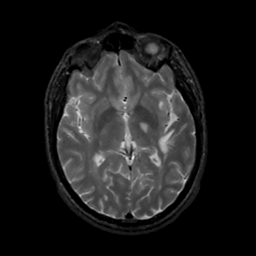

MR Study #8, March 31, 1991 -- Slice #25